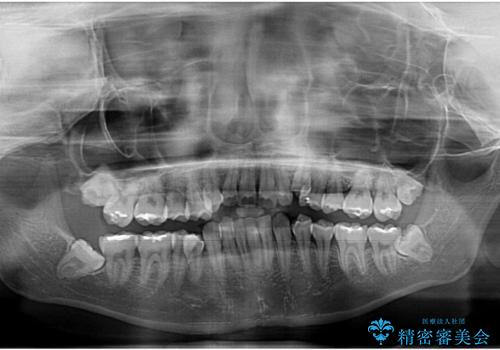

骨格的な左右差と、歯列から外れている歯が上下で左右非対称になっていることから、上下正中が歯1本分ずれている状態でした。

八重歯の改善と、上下の正中位置を極力合わせていくことを目的として、上下左右の第一小臼歯4本を抜歯し、ワイヤー装置にて矯正治療を行うこととしました。

アンカースクリューを用いて正中位置を調整したことで、上下の正中位置をほぼ一致させることができました。